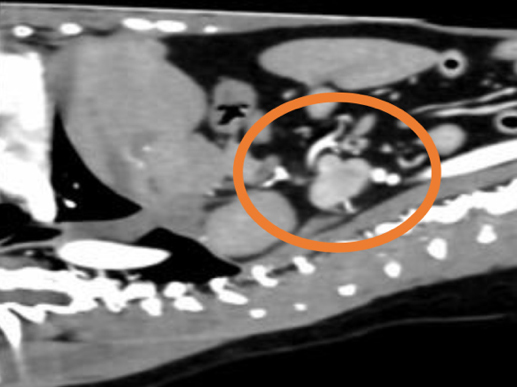

膀胱結石の精査目的で他院にてCT検査を実施したところ、左副腎に腫瘍性病変が認められ、後大静脈への浸潤も確認されました。 これを受けて、手術目的で当院を受診されました。 当院にて褐色細胞腫摘出術を実施し、術後は体調良好であったため、術後4日目に退院されました。

副腎腫瘍の中には、後大静脈などの重要な血管の中に腫瘍が入り込む(血管内浸潤)タイプがあります。このような場合、手術はさらに高度で慎重な対応が求められます。 当院では、術前にCT検査などを用いて正確な病態を把握し、安全に手術を実施する体制を整えております。必要に応じて、外科専門医や麻酔専門医がチームで対応いたします。

後大静脈に浸潤している副腎腫瘍(緑丸)